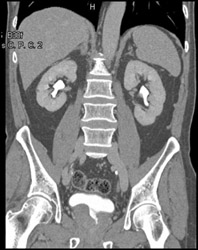

Normal CT Urogram